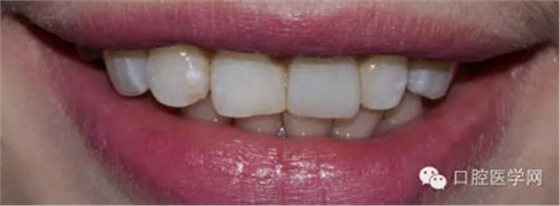

患者:女,大學(xué)生

主訴:左上門牙不好看,要求重做

現(xiàn)病史:五年前因左上門牙有扭轉(zhuǎn)不好看,有到外院做烤瓷牙,于近兩三年該牙較經(jīng)常出現(xiàn)牙齦紅腫和流血,且該牙牙齦有輕微發(fā)黑,患者還覺(jué)得該牙的顏色及形態(tài)不好看,要求重新做

檢查:21金屬烤瓷冠修復(fù),顏色及形態(tài)與鄰牙不協(xié)調(diào),牙齦有輕微發(fā)黑,扣痛(-)、松動(dòng)度(-);11近中鄰面齲壞

術(shù)前照